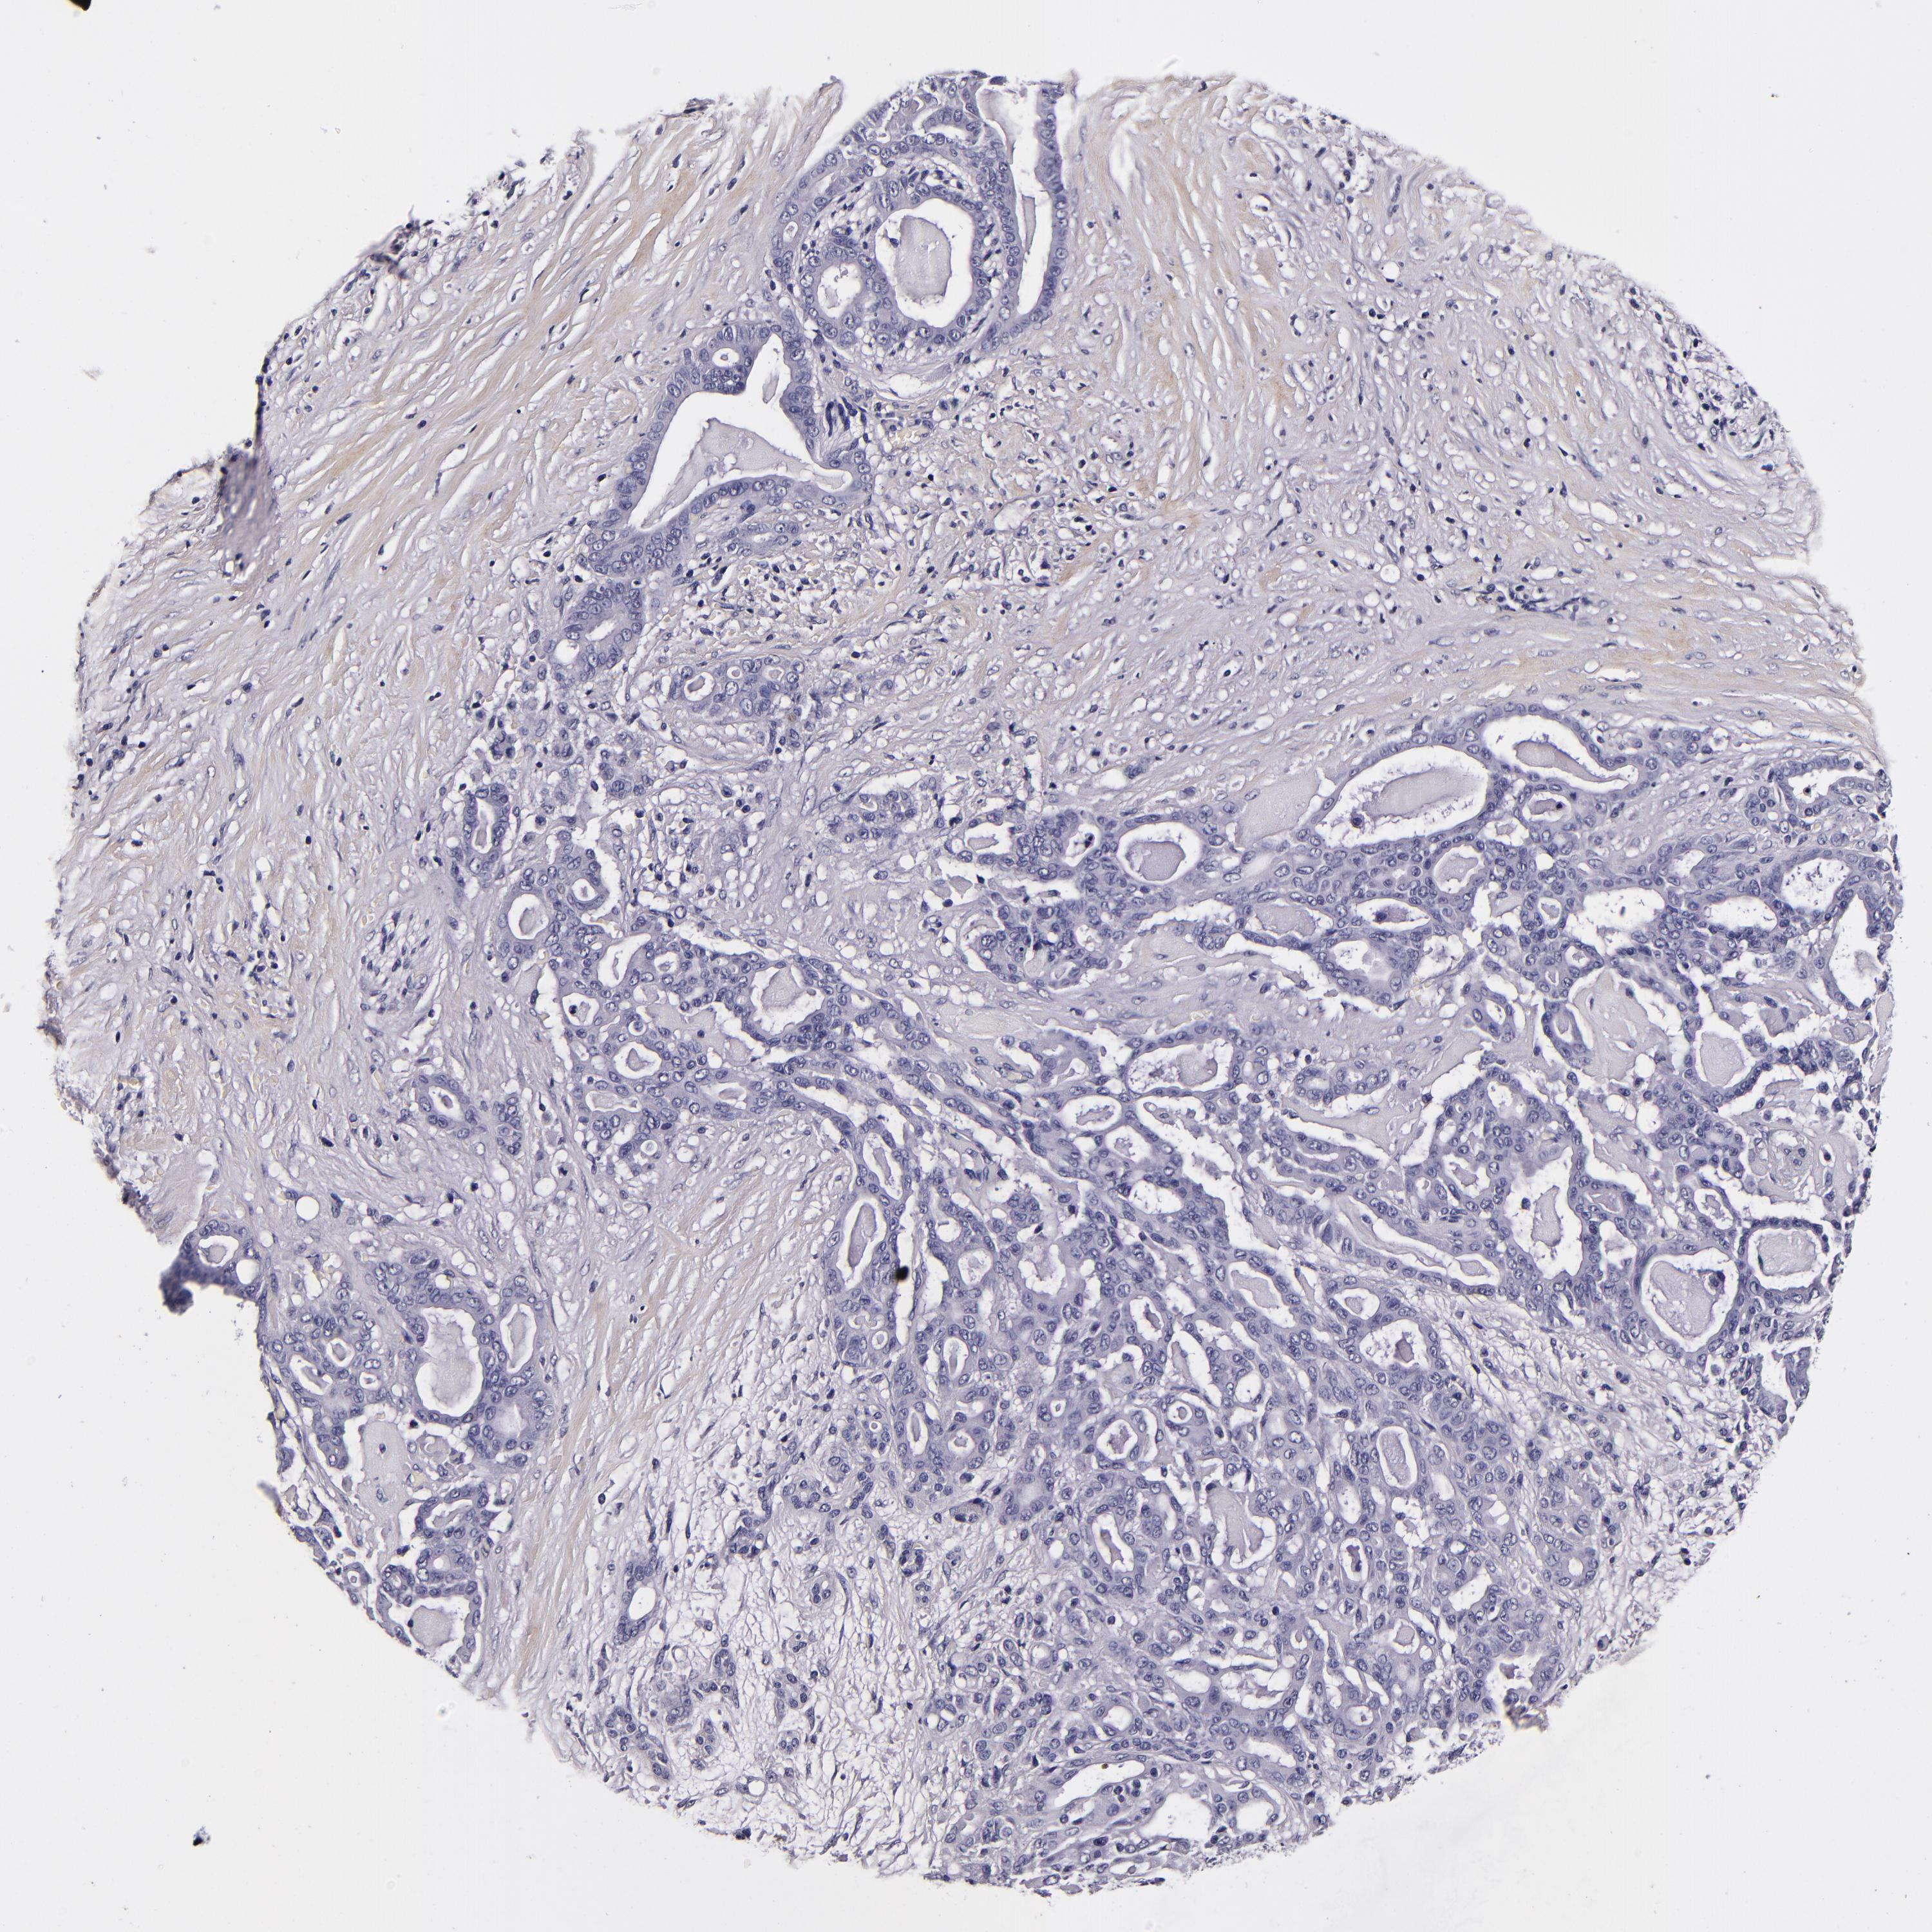

PANCREATIC CANCER - Protein expressioni

A mouse-over function shows sample information and annotation data. Click on an image to view it in a full screen mode. Samples can be filtered based on level of antibody staining by selecting one or several of the following categories: high, medium, low and not detected. The assay and annotation is described here.

Note that samples used for immunohistochemistry by the Human Protein Atlas do not correspond to samples in the TCGA dataset.

Antibody stainingi

Antibody staining in the annotated cell types in the current human tissue is reported as not detected, low, medium, or high, based on conventional immunohistochemistry profiling in selected tissues. This score is based on the combination of the staining intensity and fraction of stained cells.

Each image is clickable and will lead to virtual microscopy that enables deeper exploration of all samples and also displays staining intensity scores, fraction scores and subcellular localization as well as patient and tissue information for each sample.

HPA017759

HPA021057

CAB002670

CAB058696

CAB068188

CAB080202

Staining

High

Medium

Low

Not detected

Intensity

Strong

Moderate

Weak

Negative

Quantity

>75%

75%-25%

<25%

None

Location

Nuclear

Cytoplasmic/membranous

Cytoplasmic/membranous,nuclear

Adenocarcinoma, NOS

Adenocarcinoma, metastatic, NOS